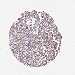

LIVER CANCER - Protein expressioni

A mouse-over function shows sample information and annotation data. Click on an image to view it in a full screen mode. Samples can be filtered based on level of antibody staining by selecting one or several of the following categories: high, medium, low and not detected. The assay and annotation is described here.

Note that samples used for immunohistochemistry by the Human Protein Atlas do not correspond to samples in the TCGA dataset.

Antibody stainingi

Antibody staining in the annotated cell types in the current human tissue is reported as not detected, low, medium, or high, based on conventional immunohistochemistry profiling in selected tissues. This score is based on the combination of the staining intensity and fraction of stained cells.

Each image is clickable and will lead to virtual microscopy that enables deeper exploration of all samples and also displays staining intensity scores, fraction scores and subcellular localization as well as patient and tissue information for each sample.

HPA046356

HPA048287

HPA050103

CAB009811

CAB032603

Staining

High

Medium

Low

Not detected

Intensity

Strong

Moderate

Weak

Negative

Quantity

>75%

75%-25%

<25%

None

Location

Nuclear

Cytoplasmic/membranous

Cytoplasmic/membranous,nuclear

Cholangiocarcinoma

Carcinoma, Hepatocellular, NOS